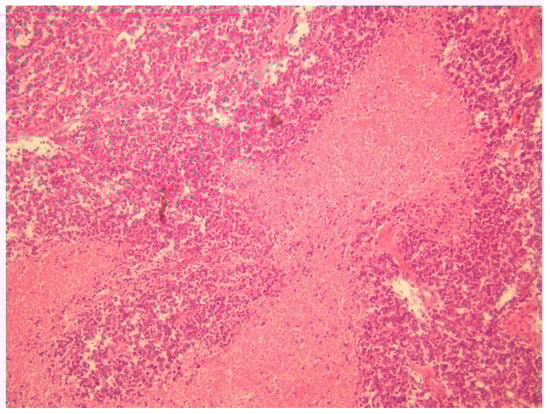

- Ewing sarcoma; this was the main one suspected, both for morphological criteria and for immunohistochemistry, too (positive CD99, cytokeratin, vimentin and FLI1).